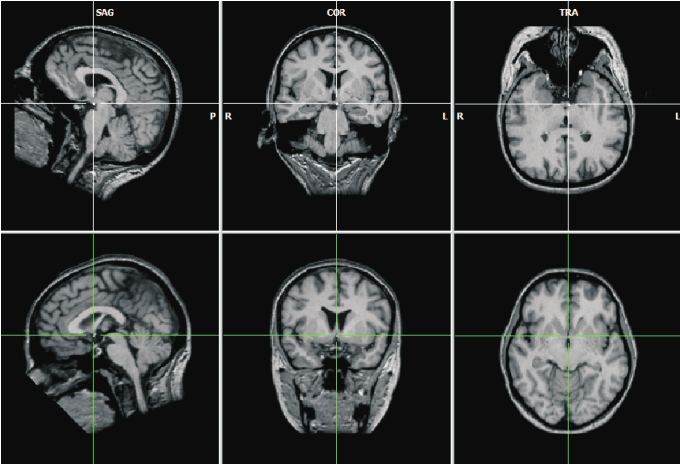

Personen die een beroerte hebben gehad, krijgen vaak ook te maken met een logopedist, omdat zij taal-, spraak- en/of slikproblemen krijgen. Sujata Soerdjbali van de Vereniging van Logopedisten in Suriname legt uit dat bij een beroerte er hersenbeschadiging plaatsvindt. “Er zijn taalgebieden in onze hersenen waar informatie over de taal wordt opgeslagen. Deze gebieden zijn gericht op het begrijpen van de taal, maar er zijn ook gebieden die gaan over het spreken van taal. Als deze gebieden beschadigd raken, kan het dus zijn dat de informatie die daar opgeslagen is, niet meer toegankelijk is.” Het kan gebeuren dat een persoon de taal wel begrijpt, maar niet meer weet wat te zeggen, maar ook kan het voorkomen dat een persoon de taal niet meer begrijpt en ook niet meer weet wat te zeggen. “Het hangt dus af van hoe ernstig de beschadiging is en ook waar die heeft plaatsgevonden.” Wat er ook gebeurt, is dat personen dan moeite krijgen met lezen en schrijven.